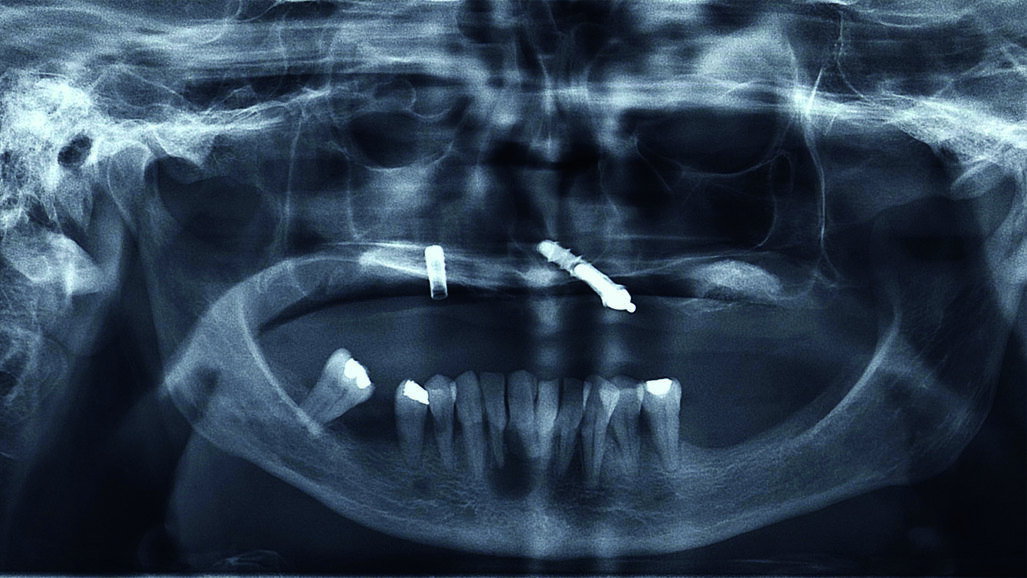

L’esame radiografico mostrava la persistenza di due impianti nel mascellare superiore (Fig. 1) uno dei quali pescava nella cavità nasale. Si osservava inoltre una lesione cistica in regione 4.1-4.2. Il trattamento dell’edentulia totale non può prescindere da una accurata analisi estetica che si concretizzerà in un’analisi Facciale, Dento-Labiale, Fonetica e Dentale. La paziente non mostrava esposizione dentale a riposo e presentava una linea del sorriso inversa (concava e non parallela al labbro inferiore) (Fig. 2). L’analisi del profilo della paziente confermava la necessità di fornire un adeguato supporto dei tessuti peri-orali nel mascellare superiore (Fig. 3). L’esame intra-orale permetteva di apprezzare l’insufficienza dell’estensione della protesi superiore, e la compromissione degli elementi dell’arcata inferiore. All’esame clinico i due impianti mostravano perdita dell’integrazione. (Figg. 4, 5).